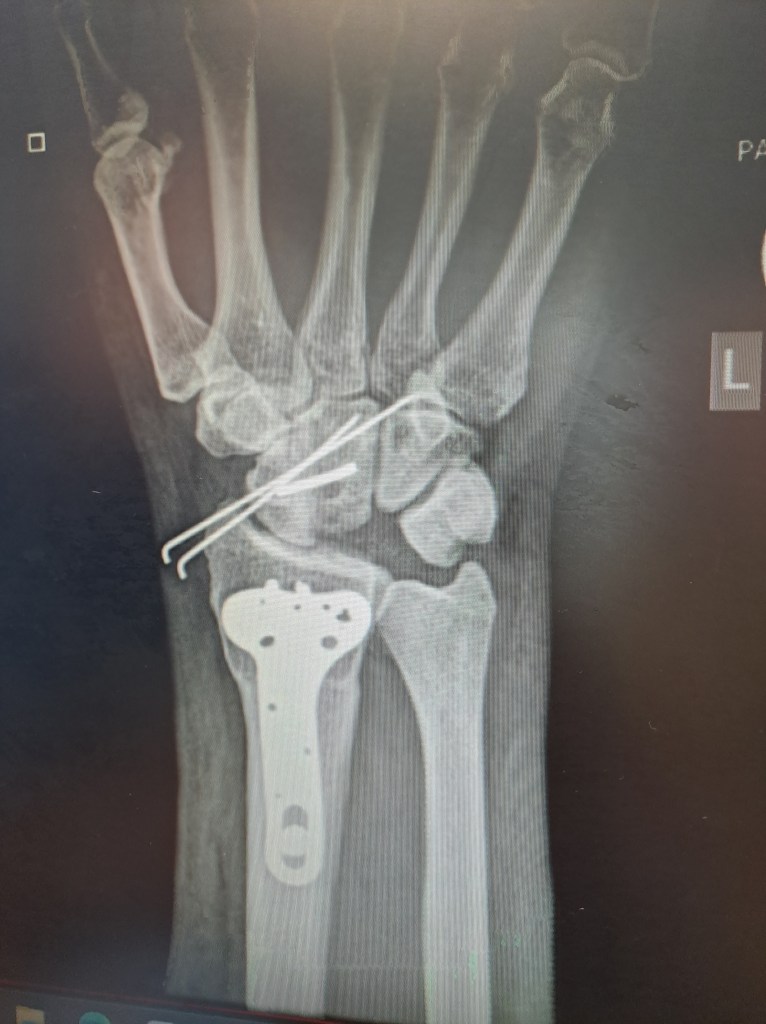

Image 3: My hand after two surgeries years apart.

Gratitude: I am so grateful to Dr. Mike Solomons who is the hand specialist who so brilliantly weaved his magic in between the bones, alive and dead.